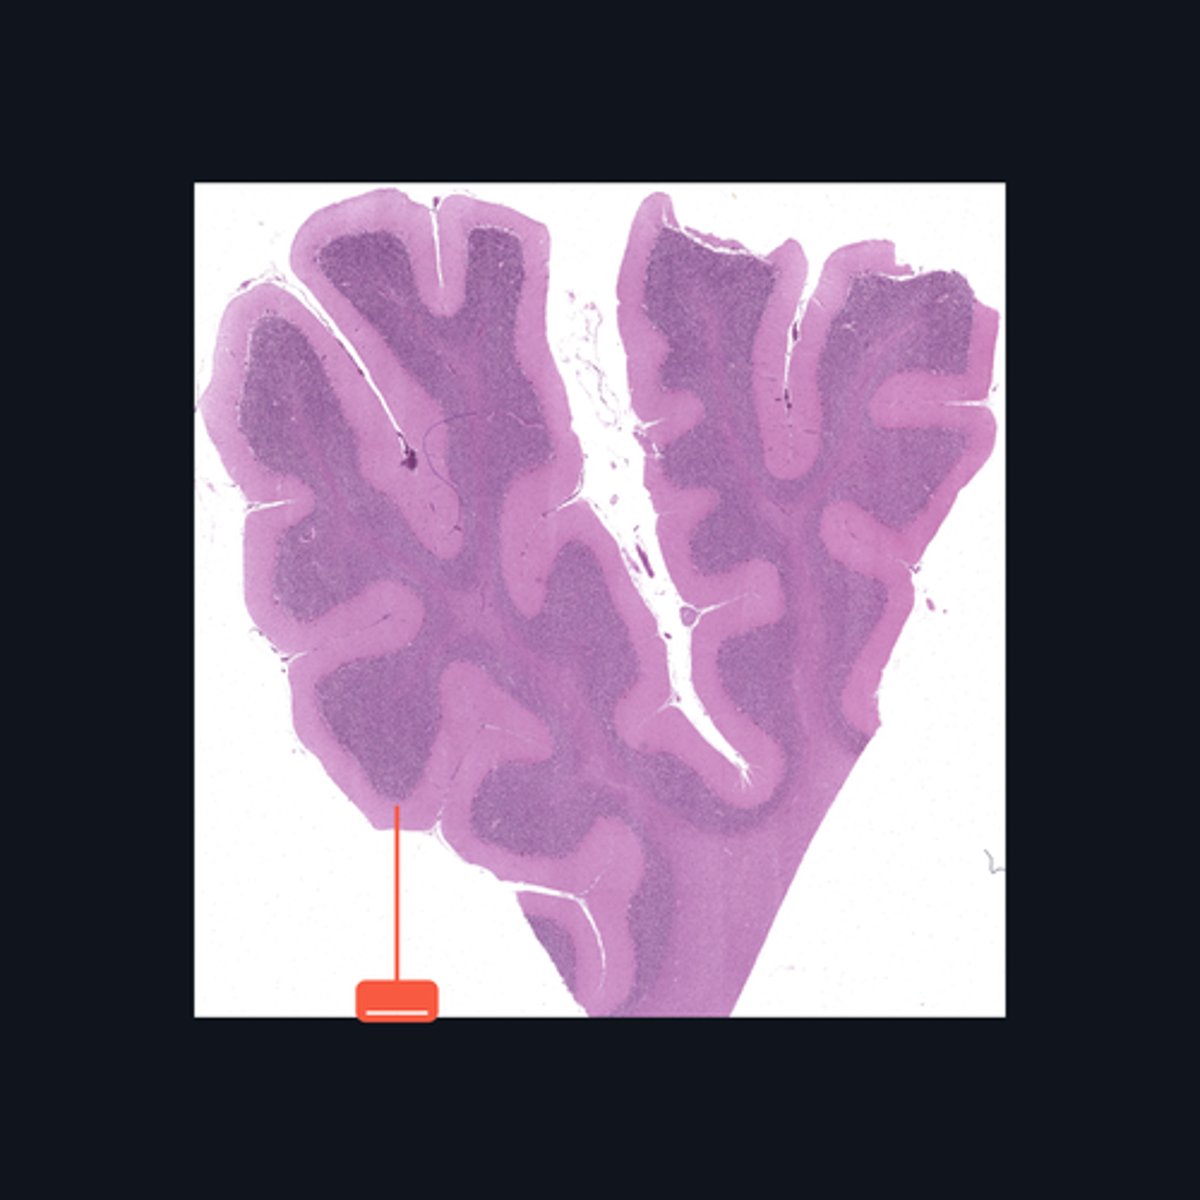

Identify the pointed region in the Cerebellum

Folia

The surface of the cerebellum exhibits transverse folds called the _____.

Purkinje cells

This middle layer of the cerebellar cortex consists of a single layer of pear-shaped multipolar neurons called _____.

Granule cells

The layer is densely populated by small, round to oval neurons called _____.